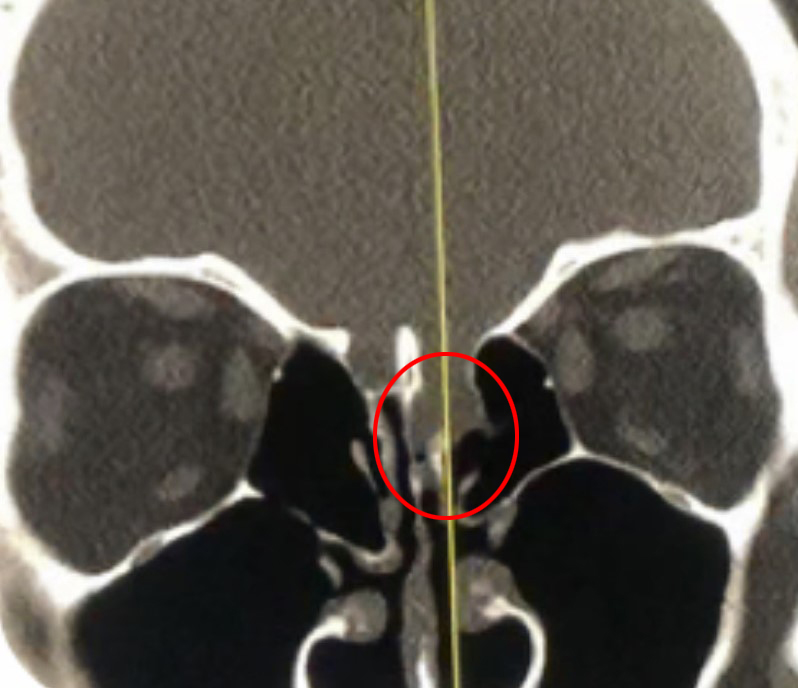

This is a 39 year old physician with a long history of sinus issues, who more recently had noted an increased drainage of clear fluid from his nose. Testing of the fluid for Beta-2-transferrin demonstrated that it was consistent with cerebrospinal fluid (csf). MRI and CT scan demonstrated an encephalocele in the frontal most part of the anterior skull base, on the left, just off midline (Figures 1a,1b,1c). For the last 3 weeks, he has also been having headaches and neck pain.

Figure 1a – Coronal CT bone window